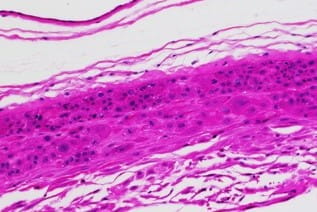

human gestational membrane immunohistochemistry H&E